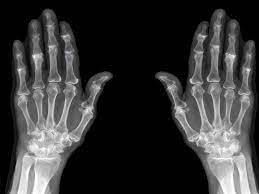

استئوآرتریت خفیف (OA) یا استئوآرتریت درجه 2، اولین درجه یا مرحله از استئوآرتریت است که در آن تغییرات قابل‌توجهی در مفاصل در عکس‌برداری با اشعه ایکس آشکار می‌شود. در این مرحله، فضای بین مفاصل شروع به باریک شدن می‌کنند، زیرا غضروف‌ها شکسته می‌شوند و استئوفیت‌ها یا خارهای استخوانی ناشی از افزایش فشار و اصطکاک در مفاصل تشکیل می‌شوند. درد و سفتی مفاصل معمولاً در مفاصل آسیب‌دیده احساس می‌شود و شواهدی از آرتروز خفیف در عکس‌برداری با اشعه ایکس قابل مشاهده است.

OA خفیف یا استئوآرتریت درجه 2 با میزان آسیب مفصلی که از طریق اشعه ایکس مشاهده می‌شود از سایر مراحل استئوآرتریت متمایز می‌شود. در این مرحله، با شروع به کاهش فضاهای مفصلی در اثر تخریب غضروف، آسیب مفصل آشکار می‌شود.

غضروف انتهای استخوان‌ها را در مفاصل می‌پوشاند و بالشتکی محافظ و ضدضربه را فراهم می‌کند. همان‌طور که غضروف شروع به شکستن و فرسودگی می‌کند، فضای داخلی مفاصل نیز کوچک‌تر می‌شود. این امر باعث افزایش اصطکاک بین استخوان‌ها می‌شود که می‌تواند منجر به ایجاد خارهای استخوانی شود.